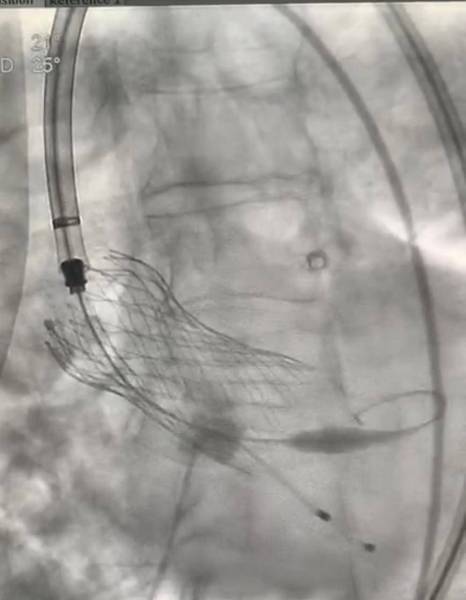

نجح الفريق الطبي بمركز الأمير سلطان لمعالجة أمراض وجراحة القلب، في إجراء عملية تغيير صمام الأورطي بالقسطرة لمسن سعودي يبلغ من العمر 118 عاما، وتعتبر أول عملية تجرى لمريض بهذا العمر على مستوى العالم عن طريق فريق طبي سعودي بالكامل بقيادة استشاري أمراض القلب والقسطرة القلبية التداخلية وقسطرة الشرايين الطرفية الدكتور بدر الزهراني.

وقال الدكتور بدر الزهراني لـ"عكاظ" أنه تم استخدام التقنيات الجديدة في تغيير الصمام الأورطي للمريض والذي يبلغ من العمر 118عاما بالقسطرة دون تدخل جراحي، مضيفا أنه لا يوجد جراح يقوم بعملية قلب مفتوح لمريض بهذا العمر لأن نسبة الخطورة عالية، لكن بفضل التقنية الجديدة والدراسات التي عملت الآن يتم عملية القسطرة للصمام الأورطي دون تدخل جراحي.

وأشار الدكتور الزهراني أن المريض تم نقله بالإخلاء الطبي من بيشة إلى مدينة الرياض وتم تقييم الحالة قبل عملية القسطرة بإجراء الفحوصات الدموية والإشاعات المقطعية والصوتية للقلب.

مشيرا أن عملية القسطرة للمريض تم إجراؤها أمس (الثلاثاء) واستغرقت ساعة و15 دقيقة، والمريض الآن في حالة صحية جيدة ومن المتوقع خروجه من المركز يوم غد (الخميس).